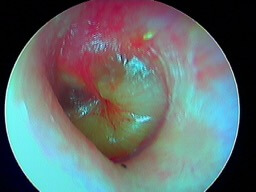

Cas particulier de l'otite externe à champignons ou otomycose

Ici une otomycose à Aspergillus niger (points noirs dans le conduit auditif)